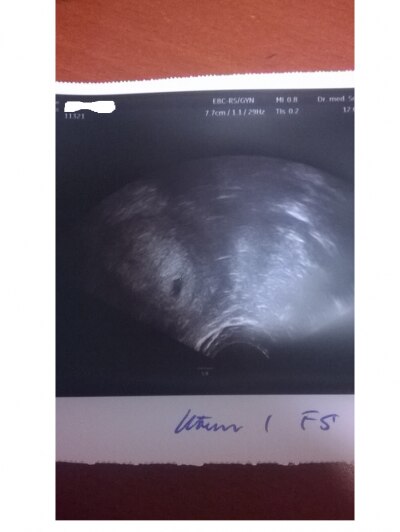

Hi war heute das zweite mal beim gyn und bis auf das er mich um 1woche zuruck datiert hat ist alles super:) bin statt 6+1 5+1 Wurde auch schon mal einer von euch zurück datiert?? Lg

Und zu der anderen frage ...siehst du auf dem bild etwas von baby? Steht doch da fruchthöhle und dottersack ...also dein poste ist ja mal mehr als Überflussig ....